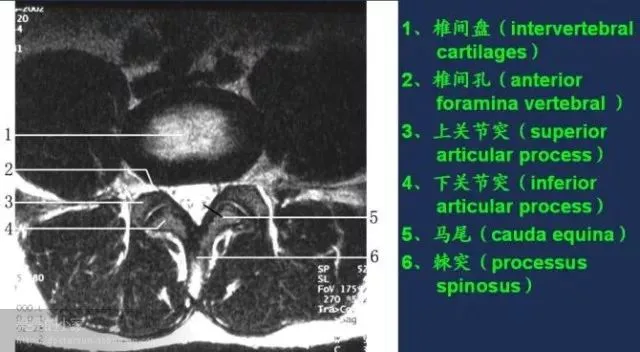

收藏!全身MRI解剖图谱,医生必备